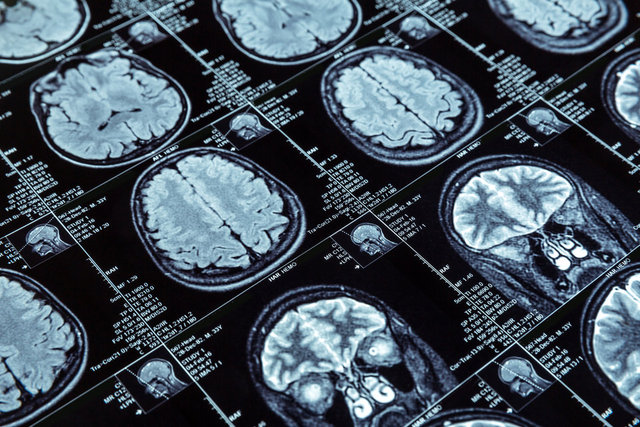

"Beyin tümörü ön tanısı alan hastalarda tümör radyolojik olarak ister iyi huylu olsun ister kötü huylu olsun öncelikli tedavinin belirlenmesi gerekir" diyen Prof. Dr. Bozkurt, sözlerine şöyle devam etti: "Günümüzde artık ister iyi huylu ister kötü huylu olsun beyin tümörlerin tedavisinde cerrahi tedavi çoğunlukla öncelikli olarak kabul edilen yaklaşım şeklidir. Özellikle bu tümörlerin tam ya da tama yakın çıkarılması ile hastalarımız için uzun ve sağlıklı bir yaşam sağlanmaktadır.”

Beyin tümörünün cerrahi tedavisinde belirleyici olan faktörleri ‘tümörün cinsi ve iyi-kötü huylu görüntüsünün olması, yerleşim yeri, büyüklüğü, hastanın yaşı, hastanın genel durumu ve performansı, hastanın nörolojik durumu, tümörün hayatı tehdit etme durumu ve hastanın operasyon kararını etkileyebilecek derecede ek sistemik problemlerin olup olmaması’ olarak açıklayan Prof. Dr. Bozkurt, “İyi huylu tümörlerin bir kısmında kötü huylu tümörlerin ise tamamına yakın bir kısmında özel bir neden olmadıkça cerrahi tedaviye ek olarak radyoterapi ve kemoterapi verilmektedir.

Ayrıca günümüzde iyi huylu tümörlerin bir kısmında ve kötü huylu tümörlerin tamamında cerrahi tedavi sonrası lokal radyoterapi uygulamalarının sonuçları bizleri oldukça mutlu etmektedir. Ayrıca cerrahi tedavi sonrası çıkarılan tümör alanına uygulanan yeni yöntemler ile yan etkiler azaltılırken bir yandan da tedavi etkinliği önemli ölçüde artırılmaktadır.

Onkoloji alanında son yıllarda geliştirilen hedefe yönelik akıllı ilaçlar beyin tümörü tedavisinde yeni umutların oluşmasına yol açmıştır. Çok yakın döneme kadar kullanılan ancak beyin tümörünün tedavisinde pek faydası olmayan kemoterapi ilaçlarının yarattığı olumsuzluk, şimdilerde hedefe yönelik akıllı ilaçlarla ortadan kalkmış ve aynı zamanda akıllı ilaçlar yapılan ameliyat ve ameliyat sonrası uygulanan radyoterapinin başarı şansını artırmıştır” dedi.